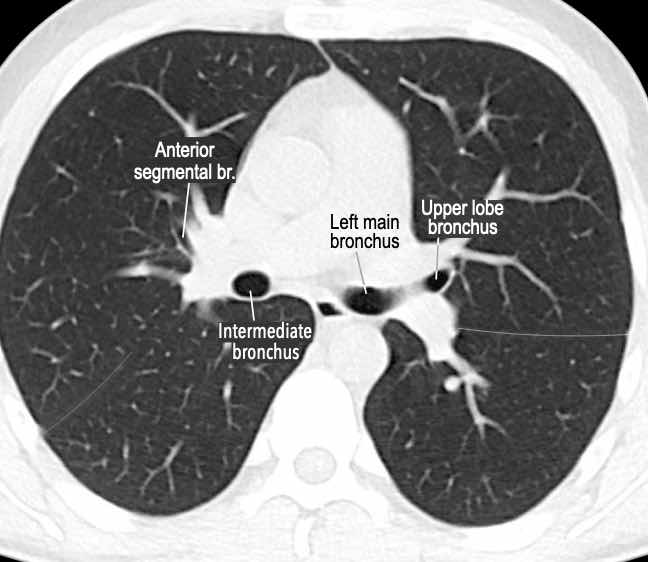

Phế quản trên CT

Cuộn qua các hình ảnh để quan sát khí quản phân chia thành phế quản chính phải và trái, sau đó tiếp tục phân chia thành các phế quản thùy và phế quản phân thùy.